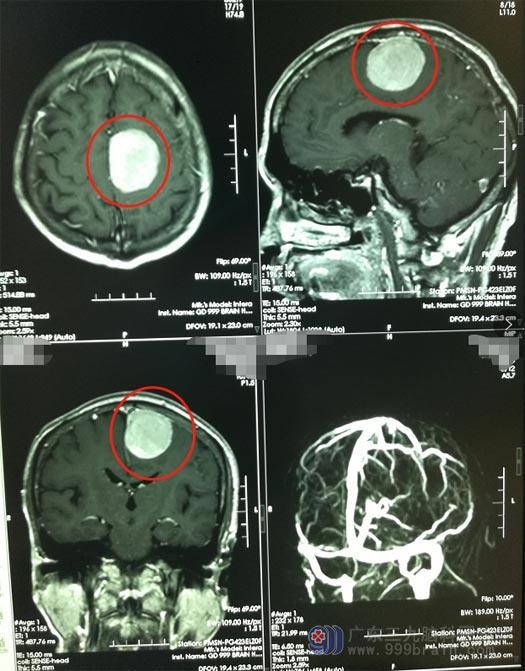

这时候,家人开始着急了,陪着吴叔去医院检查。复查颅脑MR显示“左侧额顶部脑膜瘤较前增大”;医生说,对比之前,肿瘤已经长大不少,目前已经影响到手脚活动,患者的年纪增长了,肿瘤又是在功能区,手术风险也增大了。吴叔的孩子当机立断,决定立即转院。

▲手术前